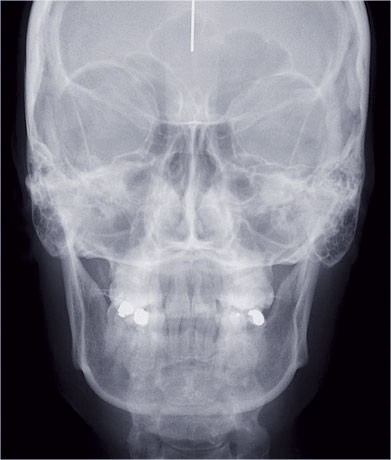

Nous lui avons donc proposé un traitement d’alignement avec maintien des 14 et 24 en position de 13 et 23 et optimisation du torque pour favoriser un développement des arcades et chercher à améliorer le sourire et le soutien labial.

Un appareillage Damon métal a été mis en place, réalisé à partir d’un set up numérique Insignia pour obtenir un contrôle précis des torques et de la forme d’arcade et réduire le temps de finition grâce à un collage indirect très précis.

Les objectifs de traitement ont été remplis. Nous avons observé un excellent contrôle du torque et une absence de perte de l’occlusion postérieure grâce à la technique Insignia.